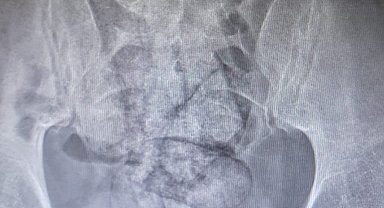

İranlı şüphelinin bağırsağından uyuşturucu çıktı